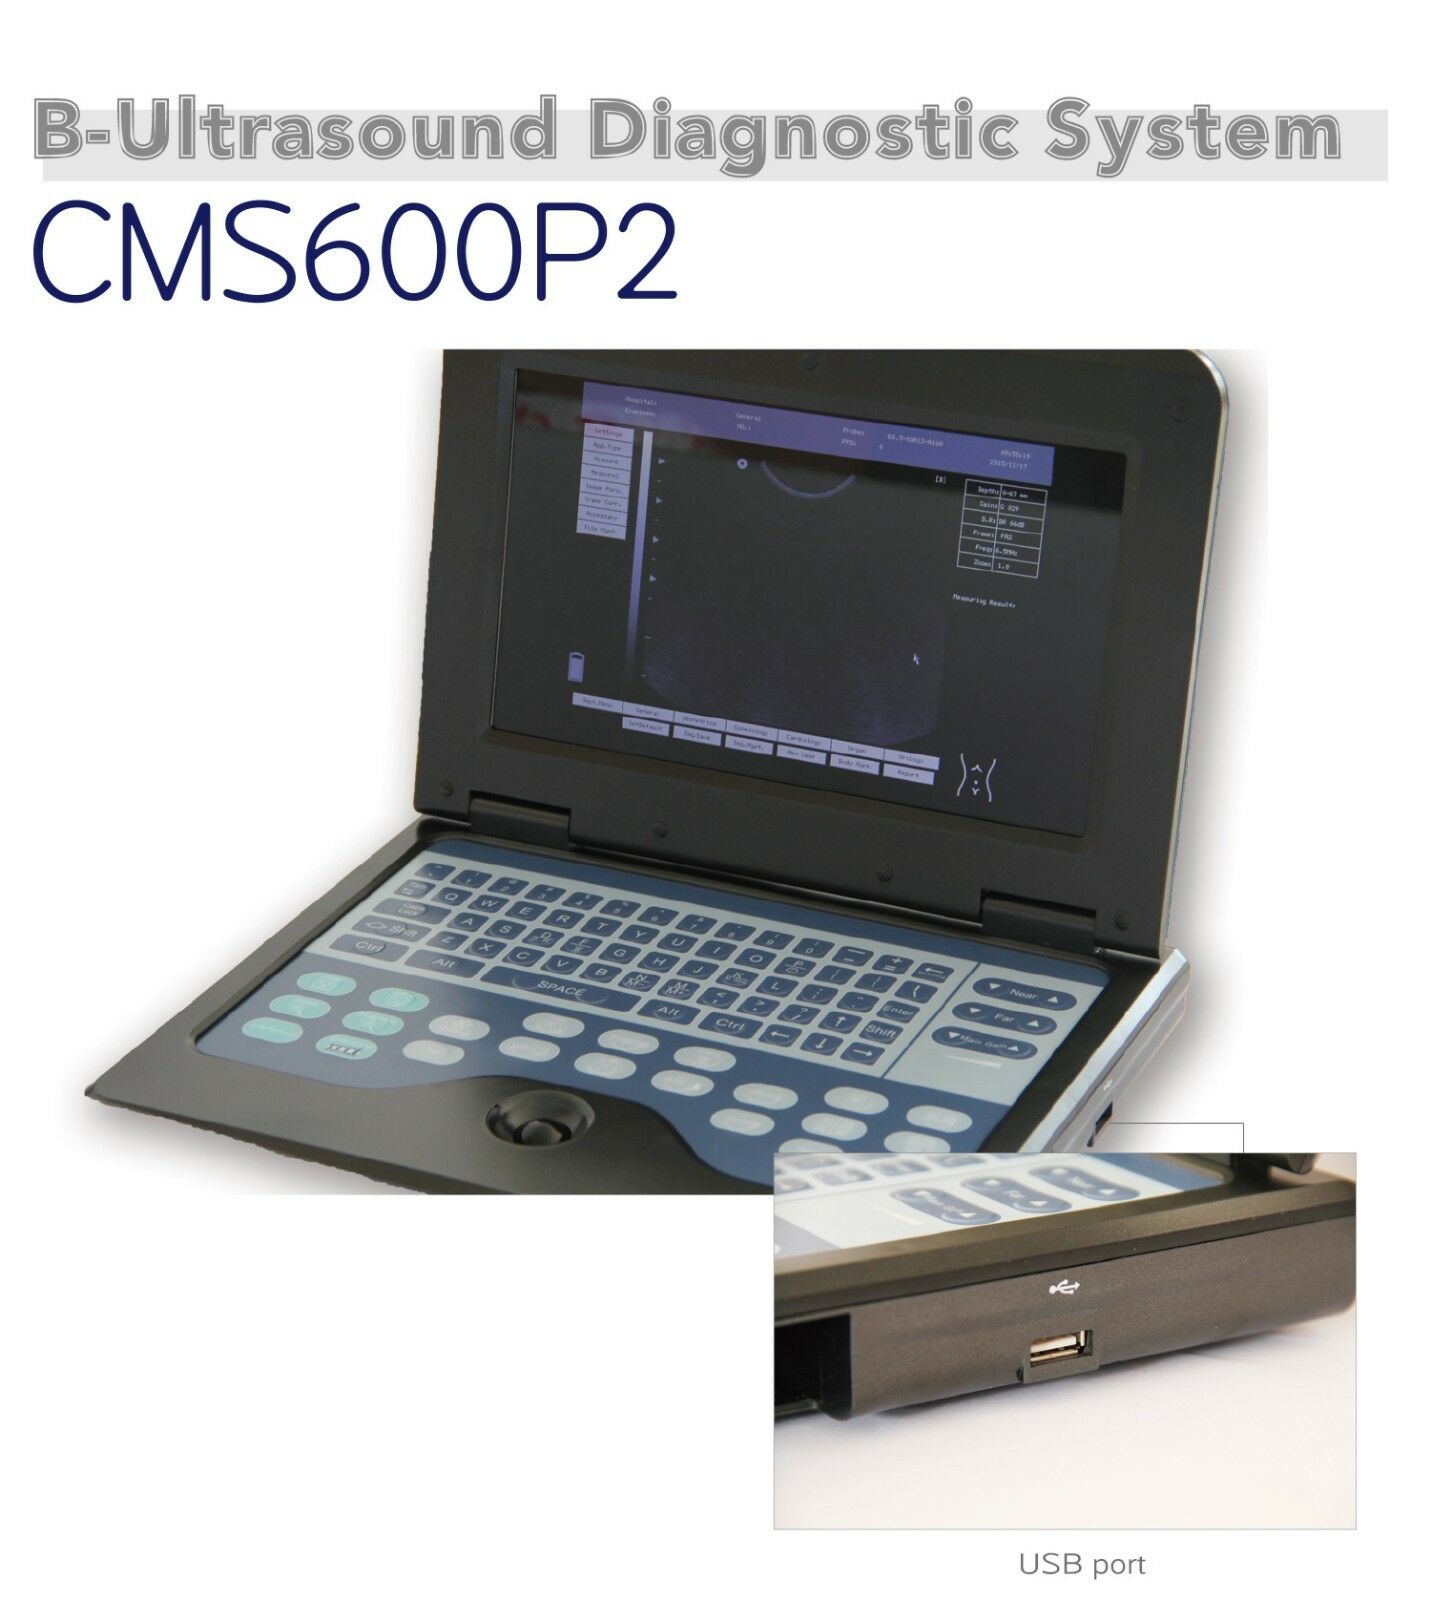

When it comes to advanced diagnostic tools, the Newest Digital Portable Laptop Ultrasound Scanner stands out. This compact and efficient device is designed to provide high-resolution images, making it an essential tool for medical professionals. The 7.5MHz Linear probe ensures detailed imaging capabilities, which can be critical in various medical examinations.

One of the key features of this ultrasound scanner is its portability. Because medical professionals often need to move between different locations, having a lightweight and portable device significantly enhances their ability to perform diagnostics on-the-go. The laptop design allows for easy transport and setup, so you can start scanning in minutes. Additionally, the digital technology integrated into this machine guarantees more precise and reliable readings compared to older models.

The Newest Digital Portable Laptop Ultrasound Scanner is not just about high-quality imaging but also about user convenience. The device is equipped with intuitive software that simplifies the diagnostic process. Medical practitioners can store and retrieve patient data efficiently, and the scanner supports various imaging modes for different diagnostic needs. This versatility makes it a valuable asset in any healthcare setting, from hospitals to private clinics.